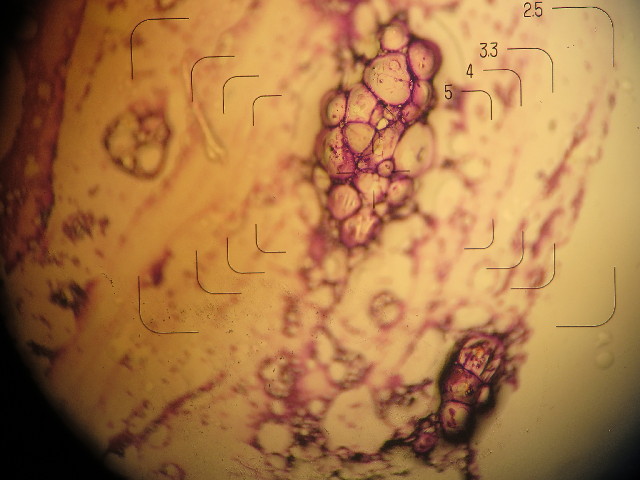

●左腕のつけのしこりを針検査してもらいました。

実は少し前にみつけていて前回も診てもらったのですが、その時は現れずに検査できませんでした。

立ったままだとわかりにくく、横になると出現(わかりやすくなる)することがわかったので、今日は最初から横になって調べてもらいました。

ここです。左腕の付け根というか、脇の下。

結果は

脂肪腫で、悪性ではないので大丈夫とのことd(^0^)b Good!!

触ったかんじ脂肪だろうとは思ったけど、扁平でコリコリしていたのでちょっと心配でした。